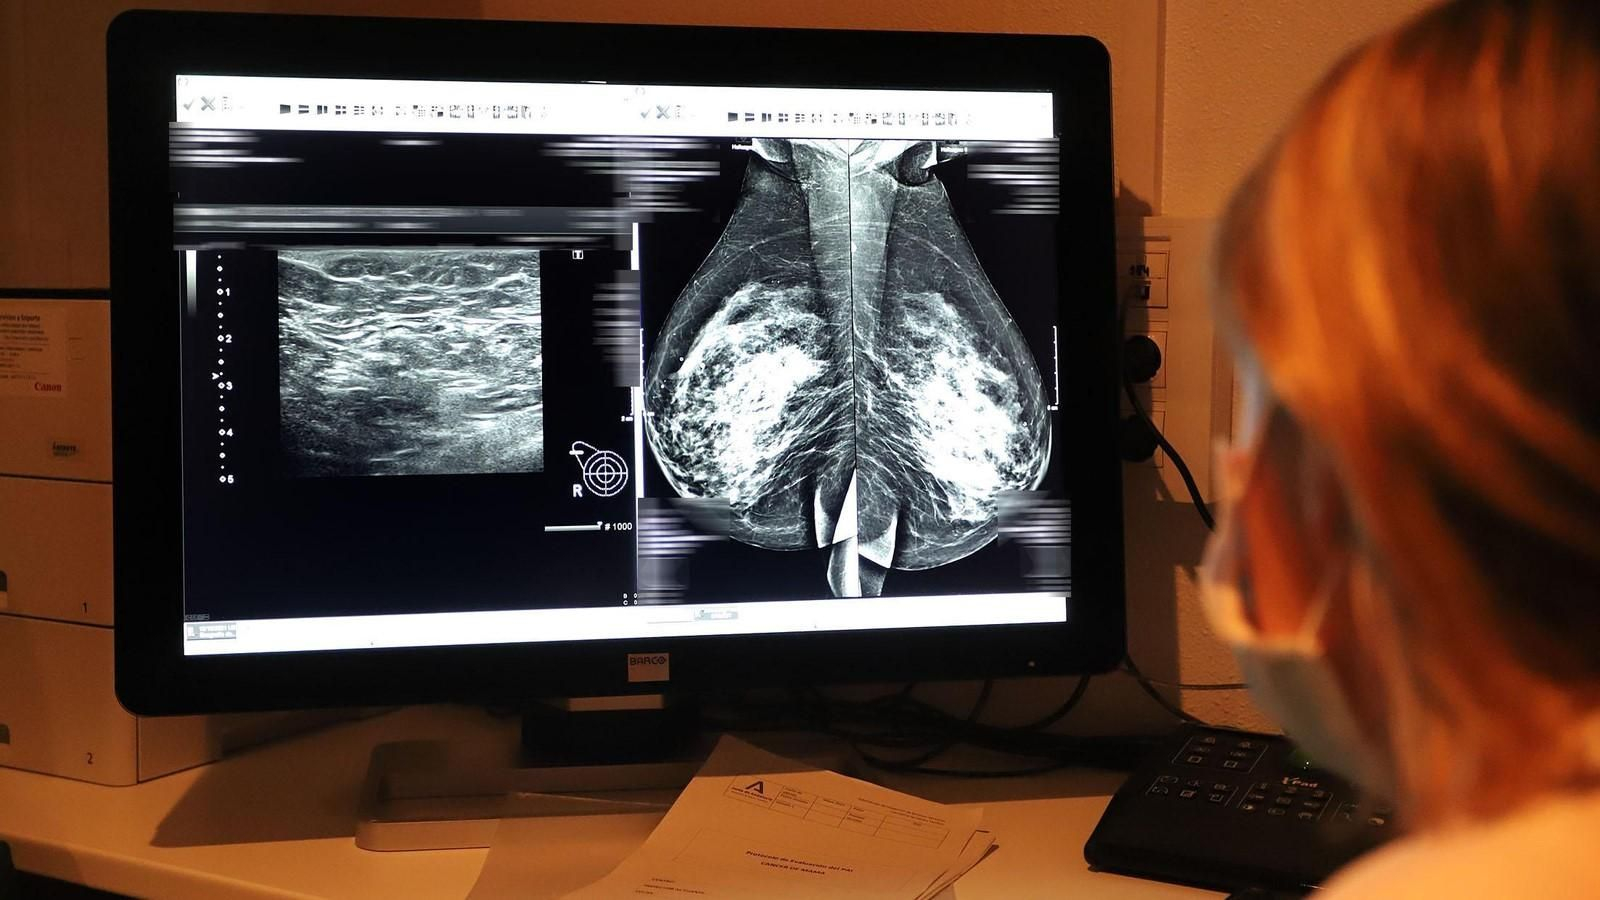

Estudio de una mamografía en un hospital.

Estudio de una mamografía en un hospital. / Alberto Domínguez